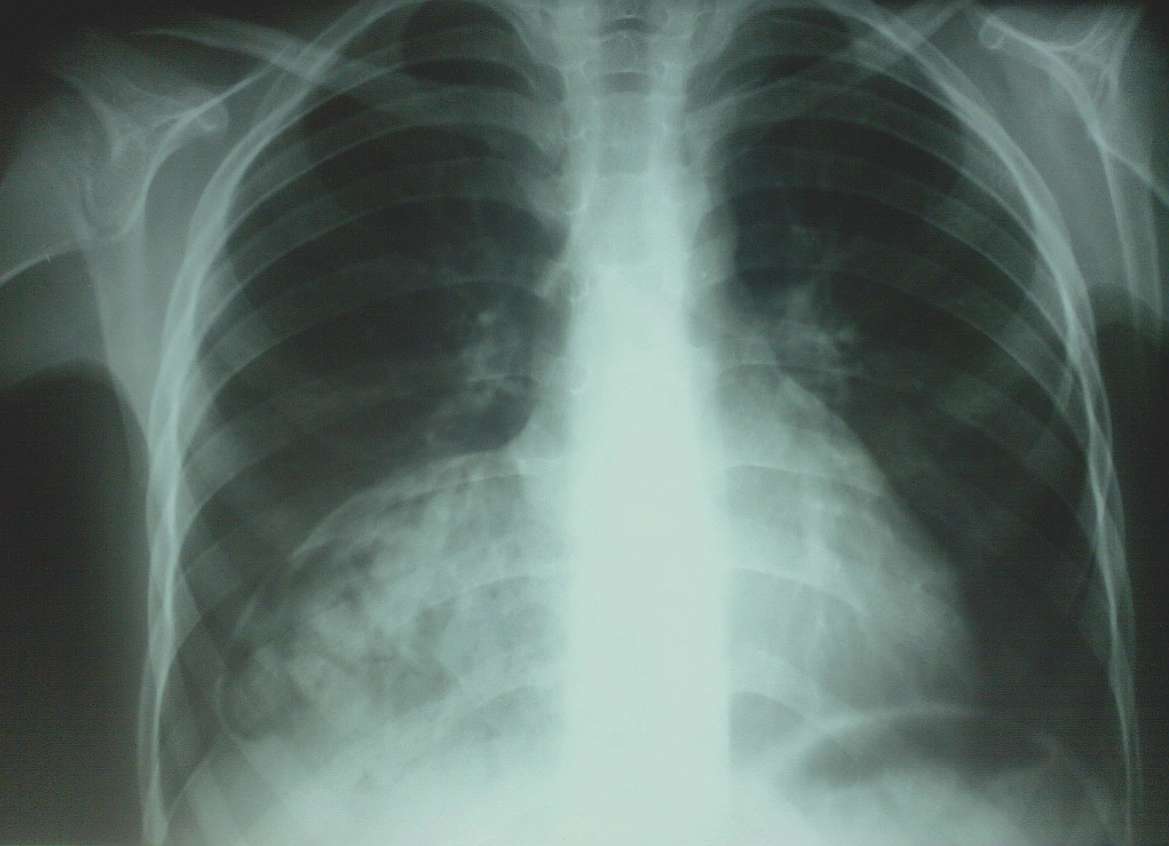

An 8-year-old girl presented to the hospital because of a light cough when she lay down. No other complains were presented by the girl and her mother.

The paediatrician found bronchial rales during auscultation in base of the right side of her chest, so he requested further imaging investigation.

What could be the diagnosis ?